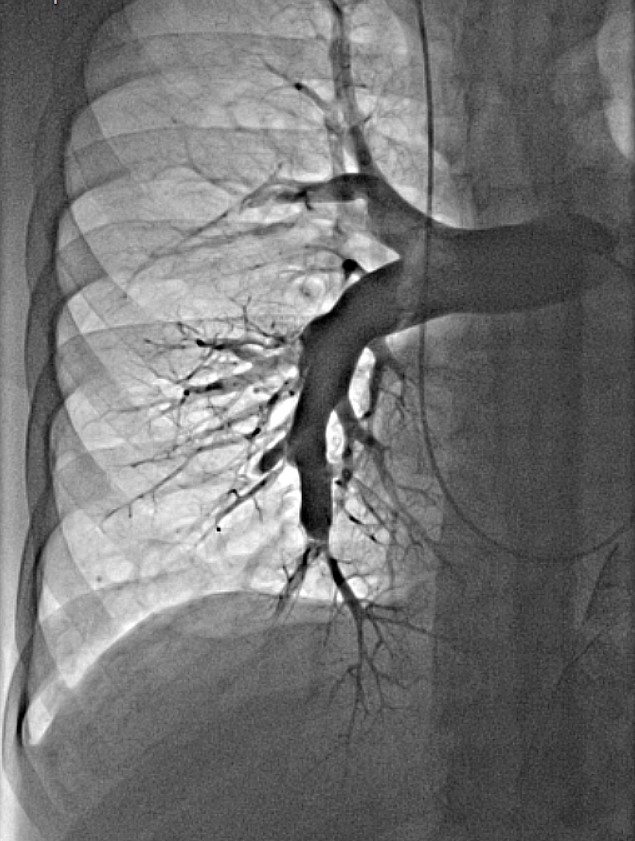

Uniwersyteckie Centrum Kliniczne oraz Gdański Uniwersytet Medyczny dołączyły do wąskiego grona ośrodków kardiologicznych w Polsce wykonujących balonoplastyki tętnic płucnych (BPA) u pacjentów z zakrzepowo-zatorowym nadciśnieniem płucnym. W związku z powyższym w Klinicznym Centrum Kardiologii UCK kierowanym przez prof. Grzegorza Raczaka rozpoczął się program inwazyjnego leczenia tej rzadkiej choroby. Pierwszy zabieg wykonał zespół w składzie: dr Dariusz Ciećwierz i dr Grzegorz Żuk pod nadzorem prof. Marcina Kurzyny z Europejskiego Centrum Zdrowia w Otwocku, który jest pionierem tych zabiegów w naszym kraju.

Zakrzepowo-zatorowe nadciśnienie płucne to stosunkowo rzadkie powikłanie ostrej zatorowości płucnej. Zgodnie z aktualnymi wytycznymi Europejskiego Towarzystwa Kardiologicznego podstawową metodą leczenia inwazyjnego tych chorych jest operacja kardiochirurgiczna. Jednakże leczenie przezskórne w postaci BPA zyskuje coraz bardziej na znaczeniu. Obecnie wykonuje się je u pacjentów, którzy zostali zdyskwalifikowani z leczenia kardiochirurgicznego lub u chorych po leczeniu operacyjnym u których nie uzyskano optymalnego efektu leczenia.

Leczenie inwazyjne w postaci BPA to leczenie wieloetapowe, rozłożone u każdego pacjenta na kilka sesji zależnie od lokalizacji zmian w krążeniu płucnym i wyników cewnikowania serca. Efekty które udaje się uzyskać na podstawie doświadczeń innych ośrodków pozwalają na istotną poprawę wydolności fizycznej pacjentów i normalizację parametrów hemodynamicznych.